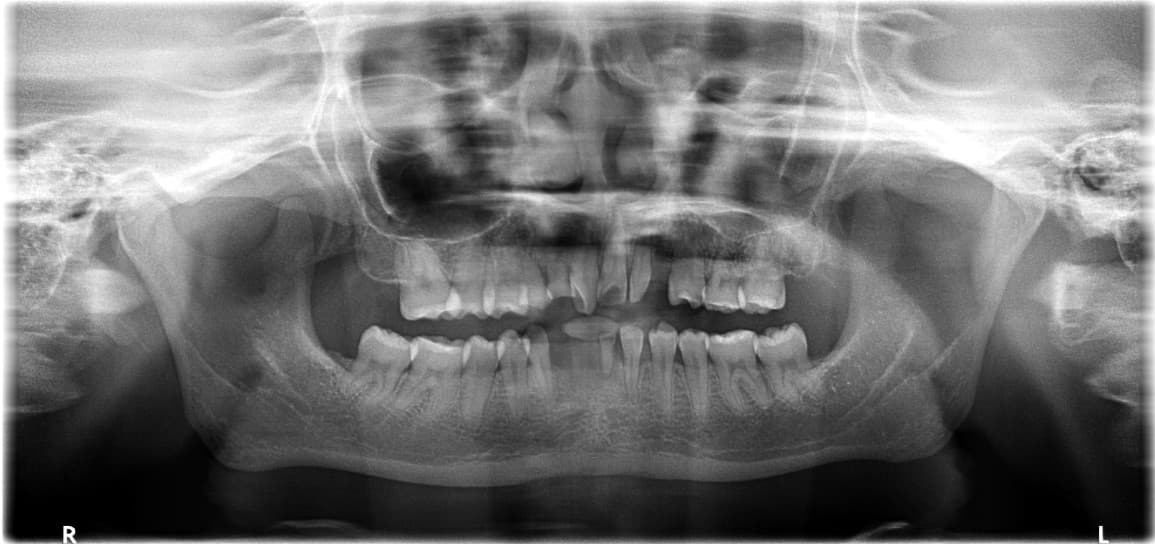

Full Mouth Reconstruction · Mr. S●● · Male, 70s

Full Mouth Reconstruction · Mr. O●● · Male, 60s